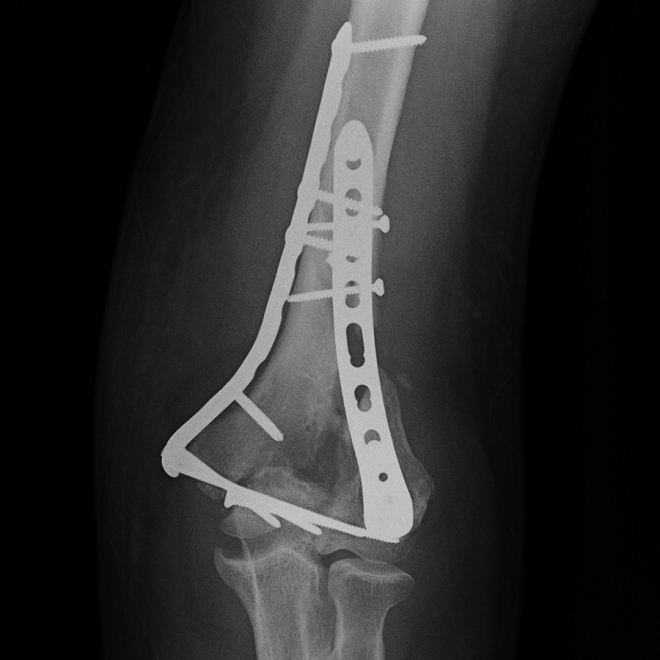

Suboptimal Dual-Energy CT. (A) Frontal radiograph demonstrates comminuted, intra-articular distal humeral fracture following open reduction and internal fixation. (B) Dual-energy CT ordered to assess fracture union provides suboptimal visualization of the intra-articular fracture site secondary to extensive, persistent artifact resulting from summation of multiple fixating screws.